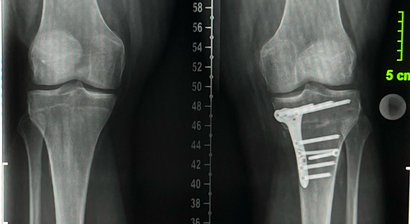

In meiner Privatordination biete ich Ihnen anhand einer ausführlichen klinischen Untersuchung sowie präziser Beurteilung der Bildgebenden Diagnostik (Röntgen, CT, MRT) eine ausführliche Erklärung Ihrer Verletzung/Diagnose die Sie verstehen!

Im Speziellen betrifft dies die Diagnose und Behandlung von akuten Verletzungen oder chronischen Schäden des Kniegelenkes. Dazu gehören insbesondere die Therapie der instabilen Kniescheibe sowie Behandlung von Bandverletzungen und Achskorrekturen bei verschiedenen Indikationen.

* Therapie von chronischen Schäden am Kniegelenk (Gelenkerhaltende Chirurgie, Osteotomie)

Osteotomie - Beinachsenkorrektur